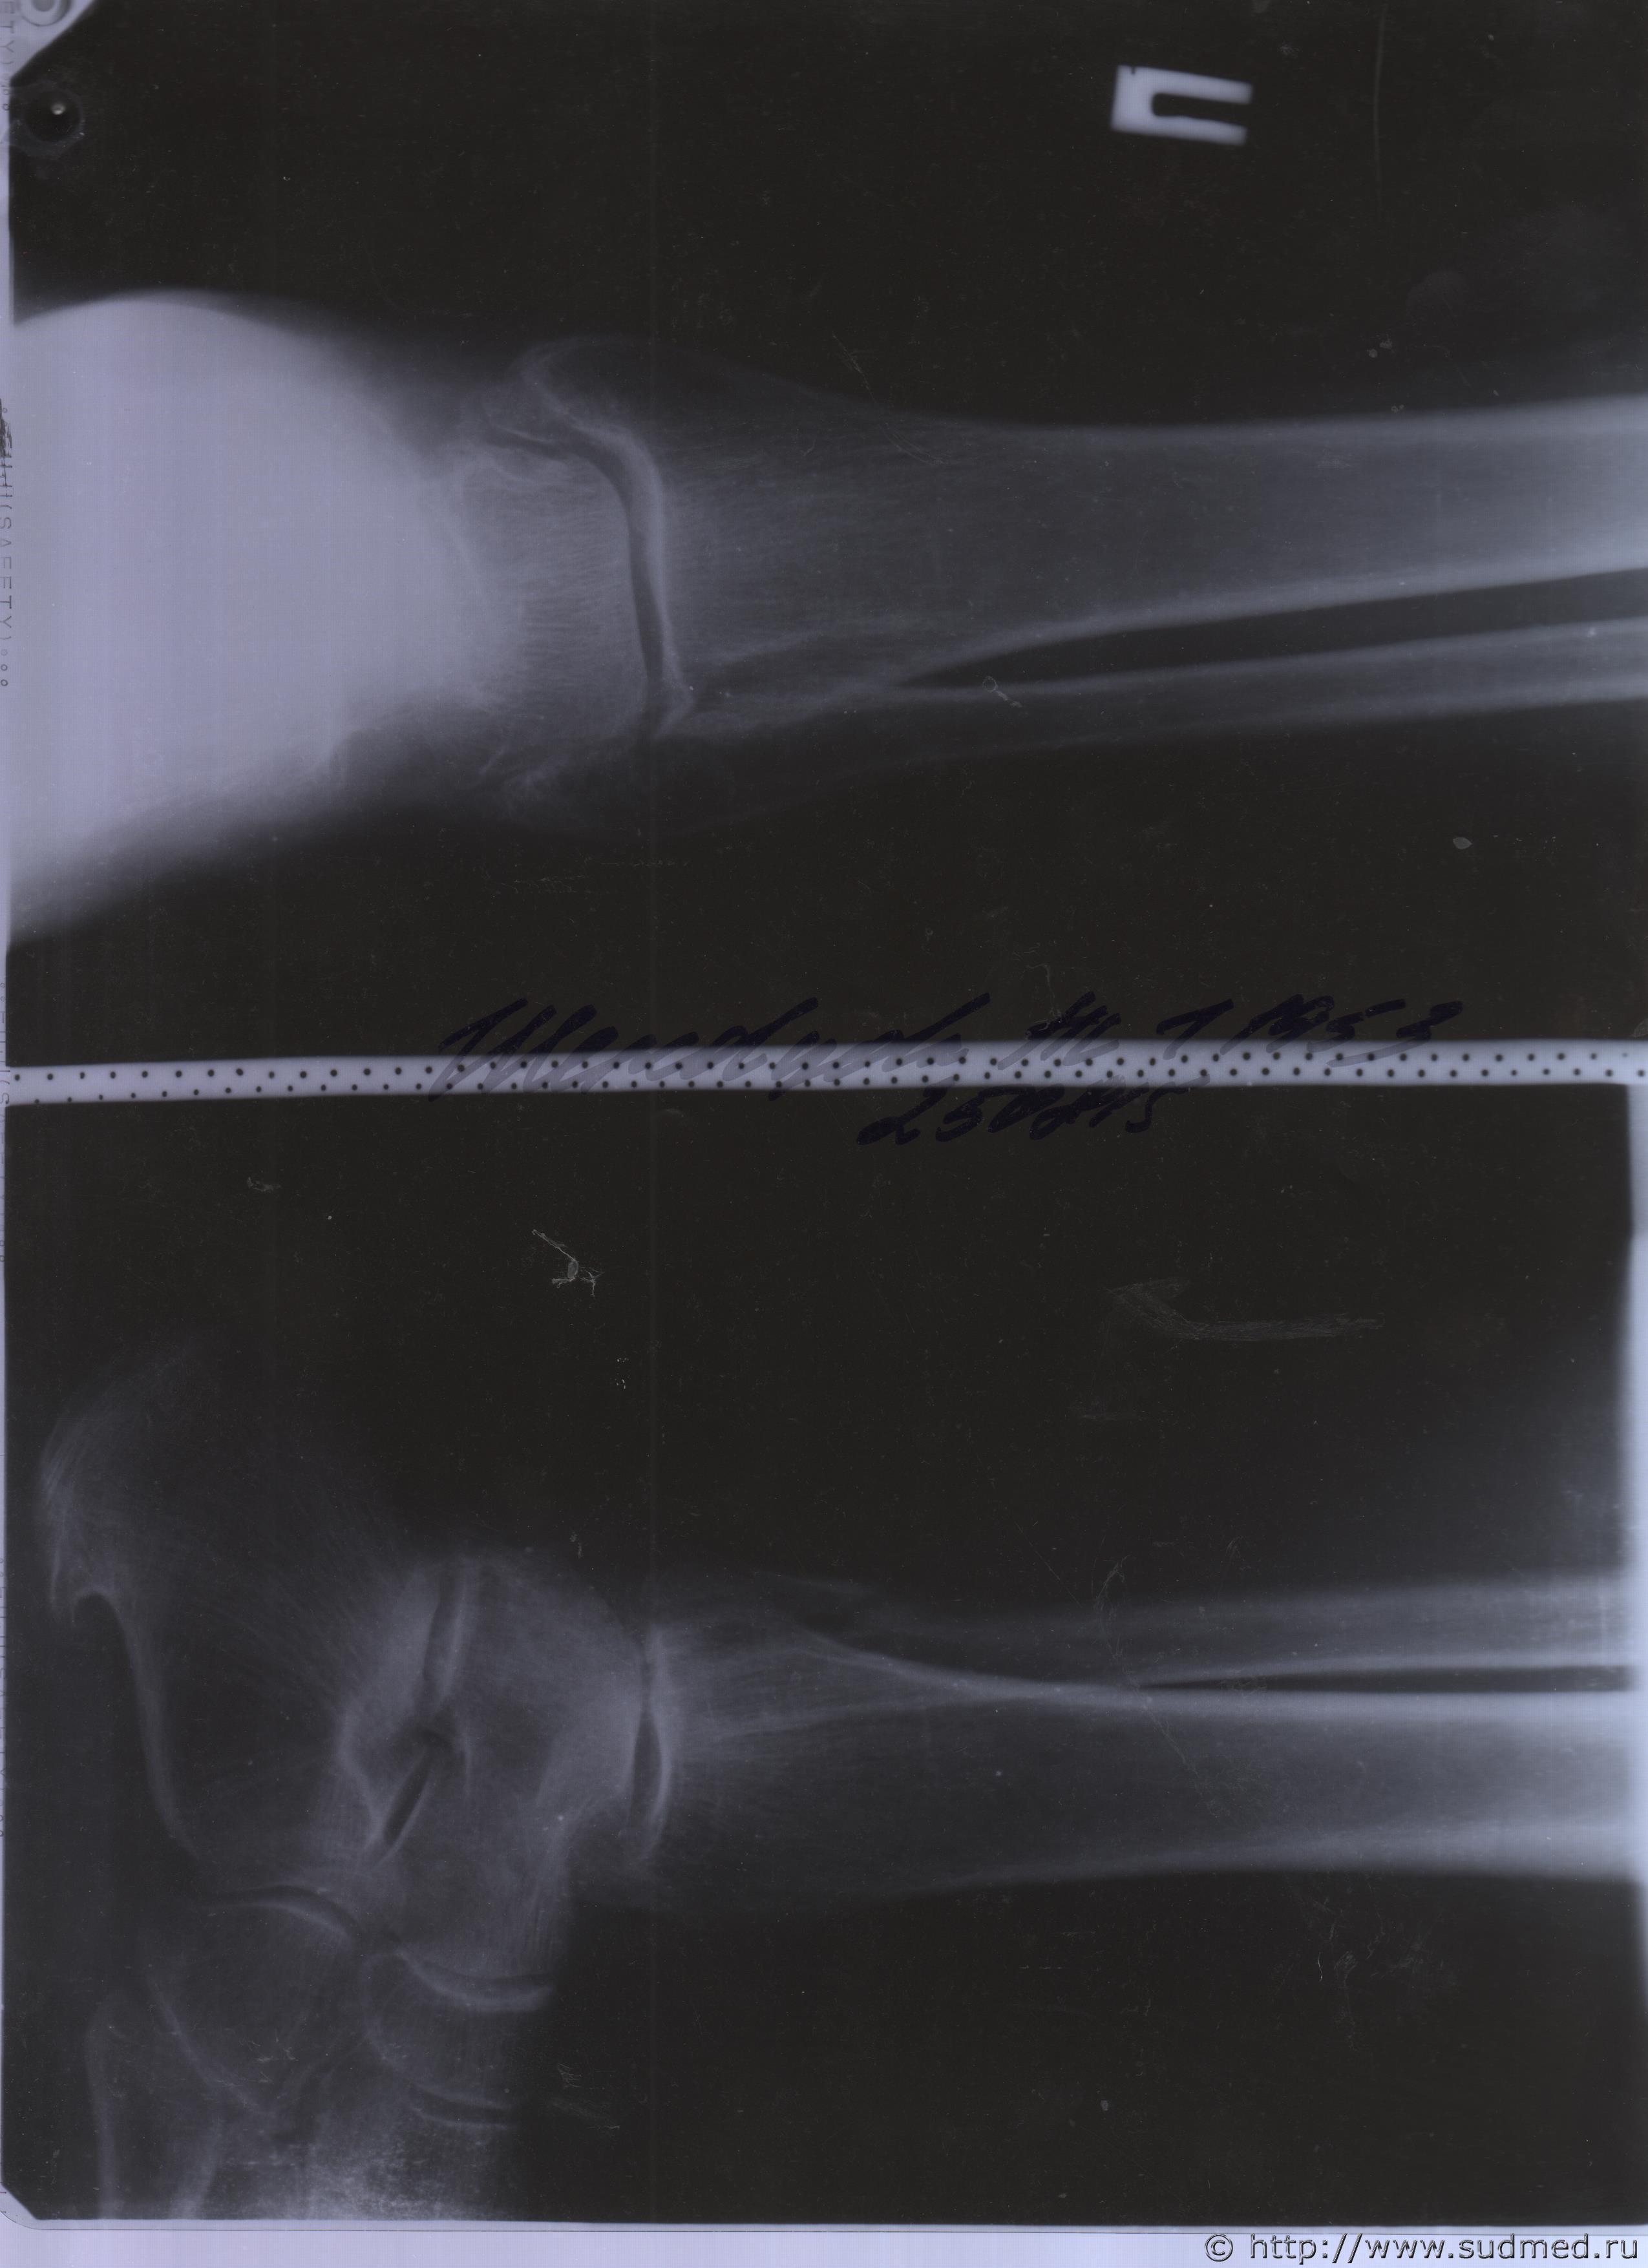

06.07.2015 г. при обращении в горбольницу мне выдали не описанный снимок( все рентгенологи были в отпуске) и справку № 4379 от 06.07.15 г. где диагноз: закрытый 2-х лодыжечный перелом правой голени без смещения. Копию справки прилагаю

За все 12 месяцев, что была на больничном, 8 раз делали снимки травмированной ноги и все заключения именно : «закрытый 2-х лодыжечный перелом правой голени без смещения».

После того, как был поставлен диагноз : «компрессионный перелом L2 позвонка поясничного отдела позвоночника». Амбулаторная мед карта, была украдена из кабинета врача травматолога. При восстановлении мед карты( в марте 2016 г.), врачом травматологом была взята копия справки от 06.07.15 г.из приемного отделения горбольницы. Справка № 4379 ( дубликат), диагноз : «закрытый 2-х лодыжечный перелом правой голени без смещения».

Посмотрите, это снимки за 12 месяцев.

Уважаемая Татьяна! По представленным Вами снимкам ничего сказать нельзя: нет маркировки даты каждого снимка (поэтому, невозможно их сравнивать друг с другом и соотносить с датой травмы), исследование непосредственно пленок гораздо более информативно, чем анализ представленных изображений (детали костной структуры в зоне перелома практически не видны).

Рекомендую проконсультировать все эти снимки у высококвалифицированного рентгенолога. Далее - по ситуации, т.е. в зависимости от его мнения. В любом случае, есть формальные основания для назначения дополнительной экспертизы, т.к., судя по представленному Вами фрагменту заключения эксперта, на экспертизу не были предоставлены все мед.документы с данными о лечении предъявляемой травмы (Вы пишете, что рентгенограммы делались на протяжении 12 месяцев, полагаю, что Вы и врачами наблюдались в течение этого срока, т.е. велась мед.карта).